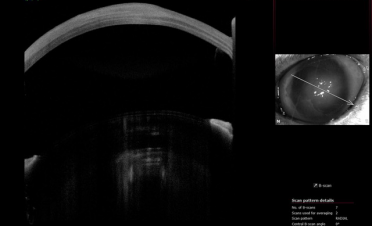

Se realizó una tomografía de coherencia óptica (OCT) para determinar el espesor de la córnea. En las imágenes se puede ver cómo el espesor de la córnea de Bagheera estaba aumentada de tamaño por la inflamación provocada por la infección.